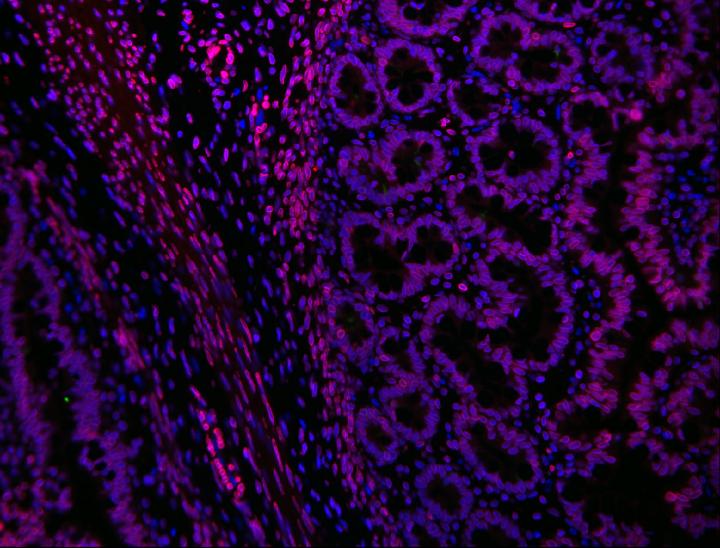

image: Human intestine, engineered in the laboratory of Tracy Grikscheit, MD.

Babies with Hirschsprung's disease are born with an incomplete or absent gut nervous system. Children's Hospital Los Angeles investigator Tracy Grikscheit, MD, runs a laboratory that investigates the therapeutic potential of tissue engineering - the induced growth of healthy tissue using stem cells. In a new study, Dr. Grikscheit successfully grew a fully functional gut nervous system - or ENS - in a pre-clinical model. While not yet available clinically, the finding brings surgeons like Dr. Grikscheit one step closer to helping babies in need.

Growing a fully functional ENS is no simple feat. "The enteric nervous system is called the second brain because it is so beautifully diverse," says Dr. Grikscheit. The ENS coordinates intestinal muscle movement, hormone release and maintenance of stem cells, which are needed to maintain the intestinal lining.